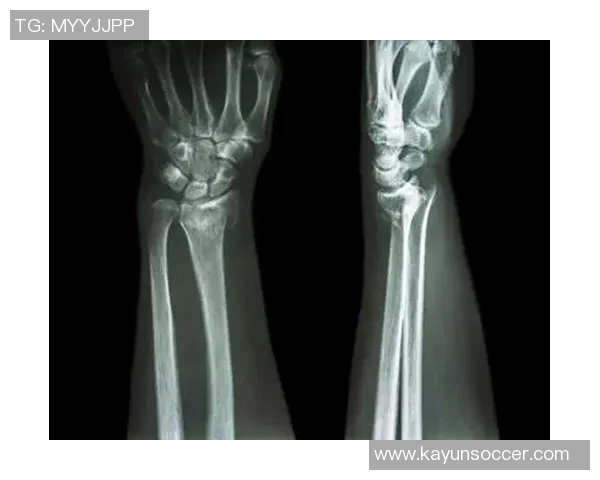

国米官方宣布迪詹纳罗右手腕骨折即将接受手术治疗

近日,国际米兰俱乐部官方宣布,球队后卫迪詹纳罗在比赛中不幸遭遇右手腕骨折,将接受手术治疗。这一消息令广大球迷感到震惊和惋惜,因为迪詹纳罗在球队中的表现一直备受期待。本文将从多个角度详细分析这一事件的影响及其对国米未来的意义,包括伤情对球队战绩的影响、球员恢复与手术前景、国米后防线的调整策略以及如何保持士气等方面,希望能为读者提供一个全面的视角。

关于迪詹纳罗即将接受手术治疗的信息,也引发了外界对于他恢复进程的广泛关注。一般而言,运动员在经历骨折后的恢复时间是相对漫长且充满挑战的。他需要进行详细检查以确保手腕骨折情况得到妥善处理。